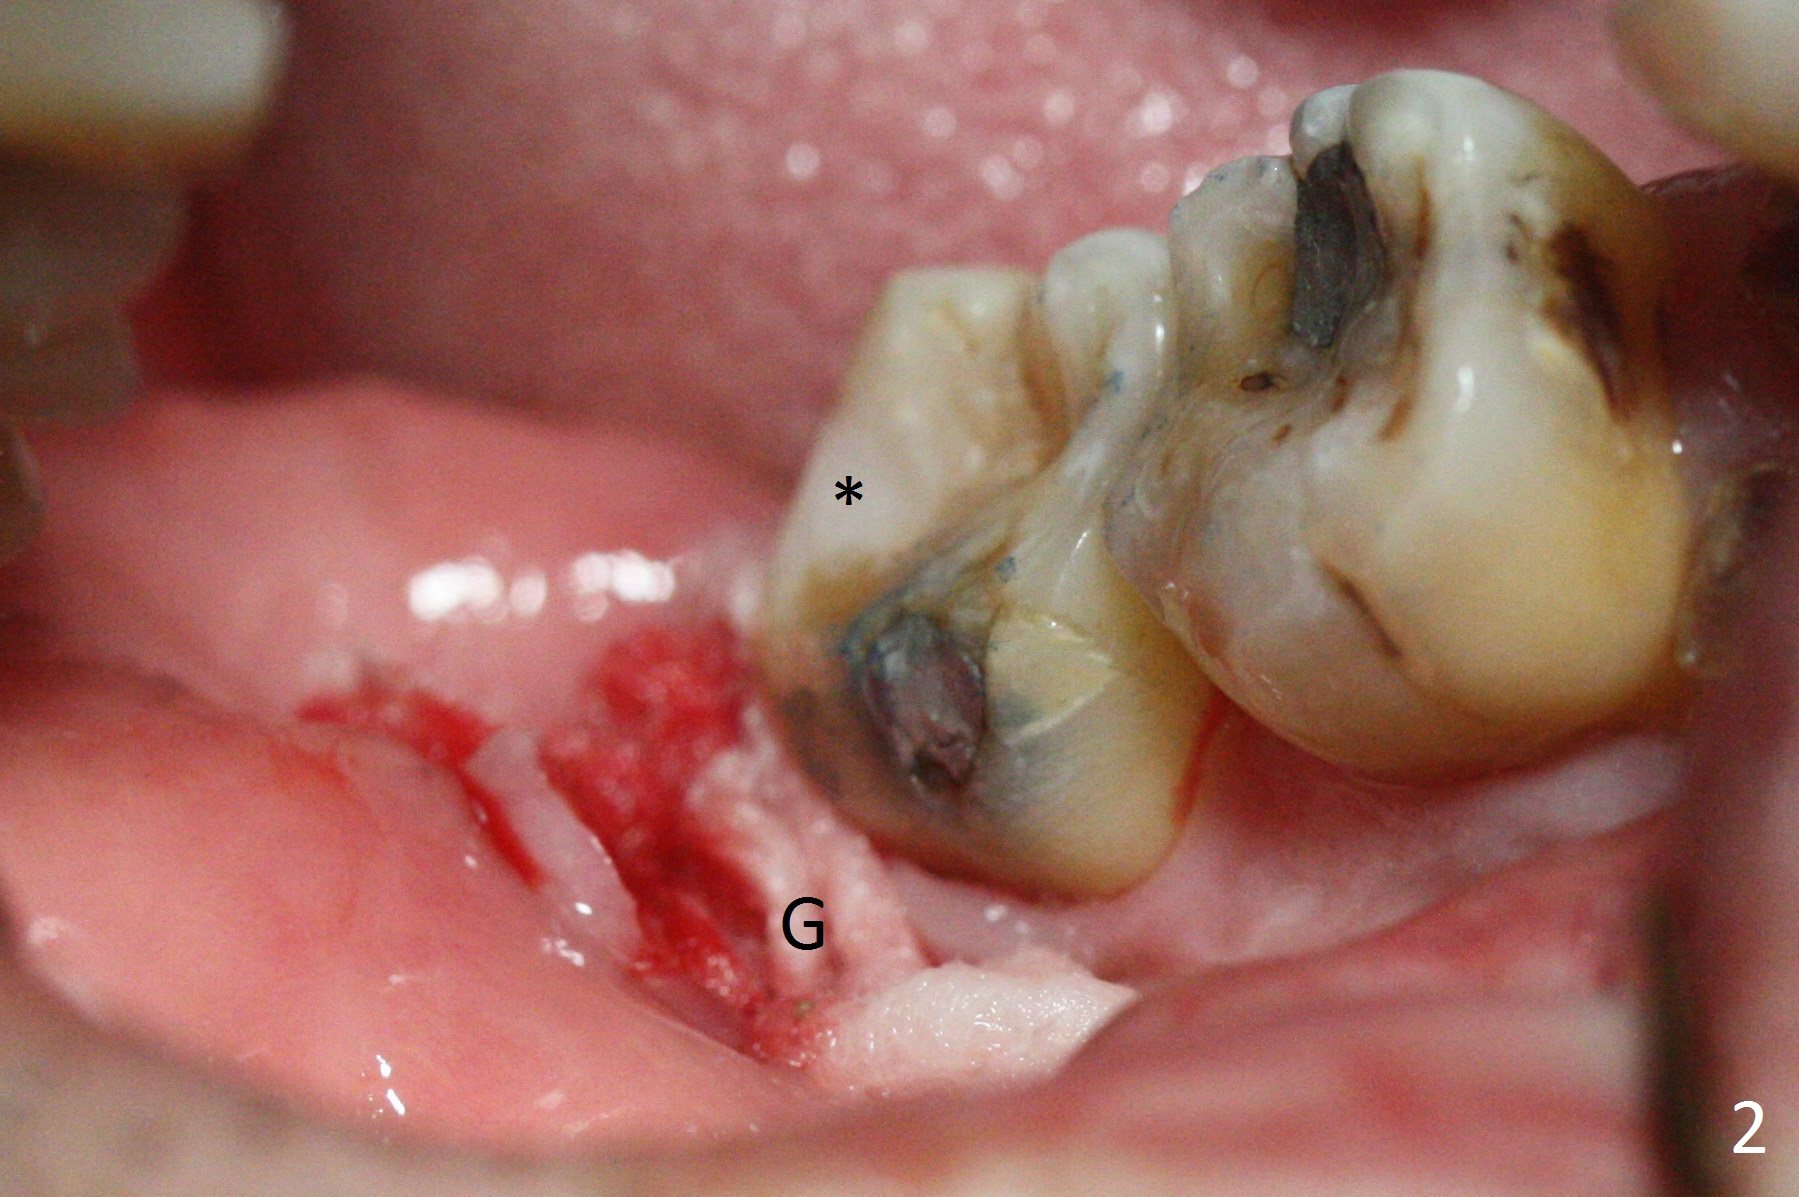

When the tooth #32 of a 47-year-old man is extracted, two pieces of 2x2 gauze (Fig.2 G) are inserted into the wound for hemostasis and composite is placed at #31 without compromise (Fig.2,3 *). Finally a 20x10 mm collagen plug is inserted into the socket of #32 prior to suturing to prevent Dry Socket. There is no leak or 2nd caries 1 year postop (Fig.4).